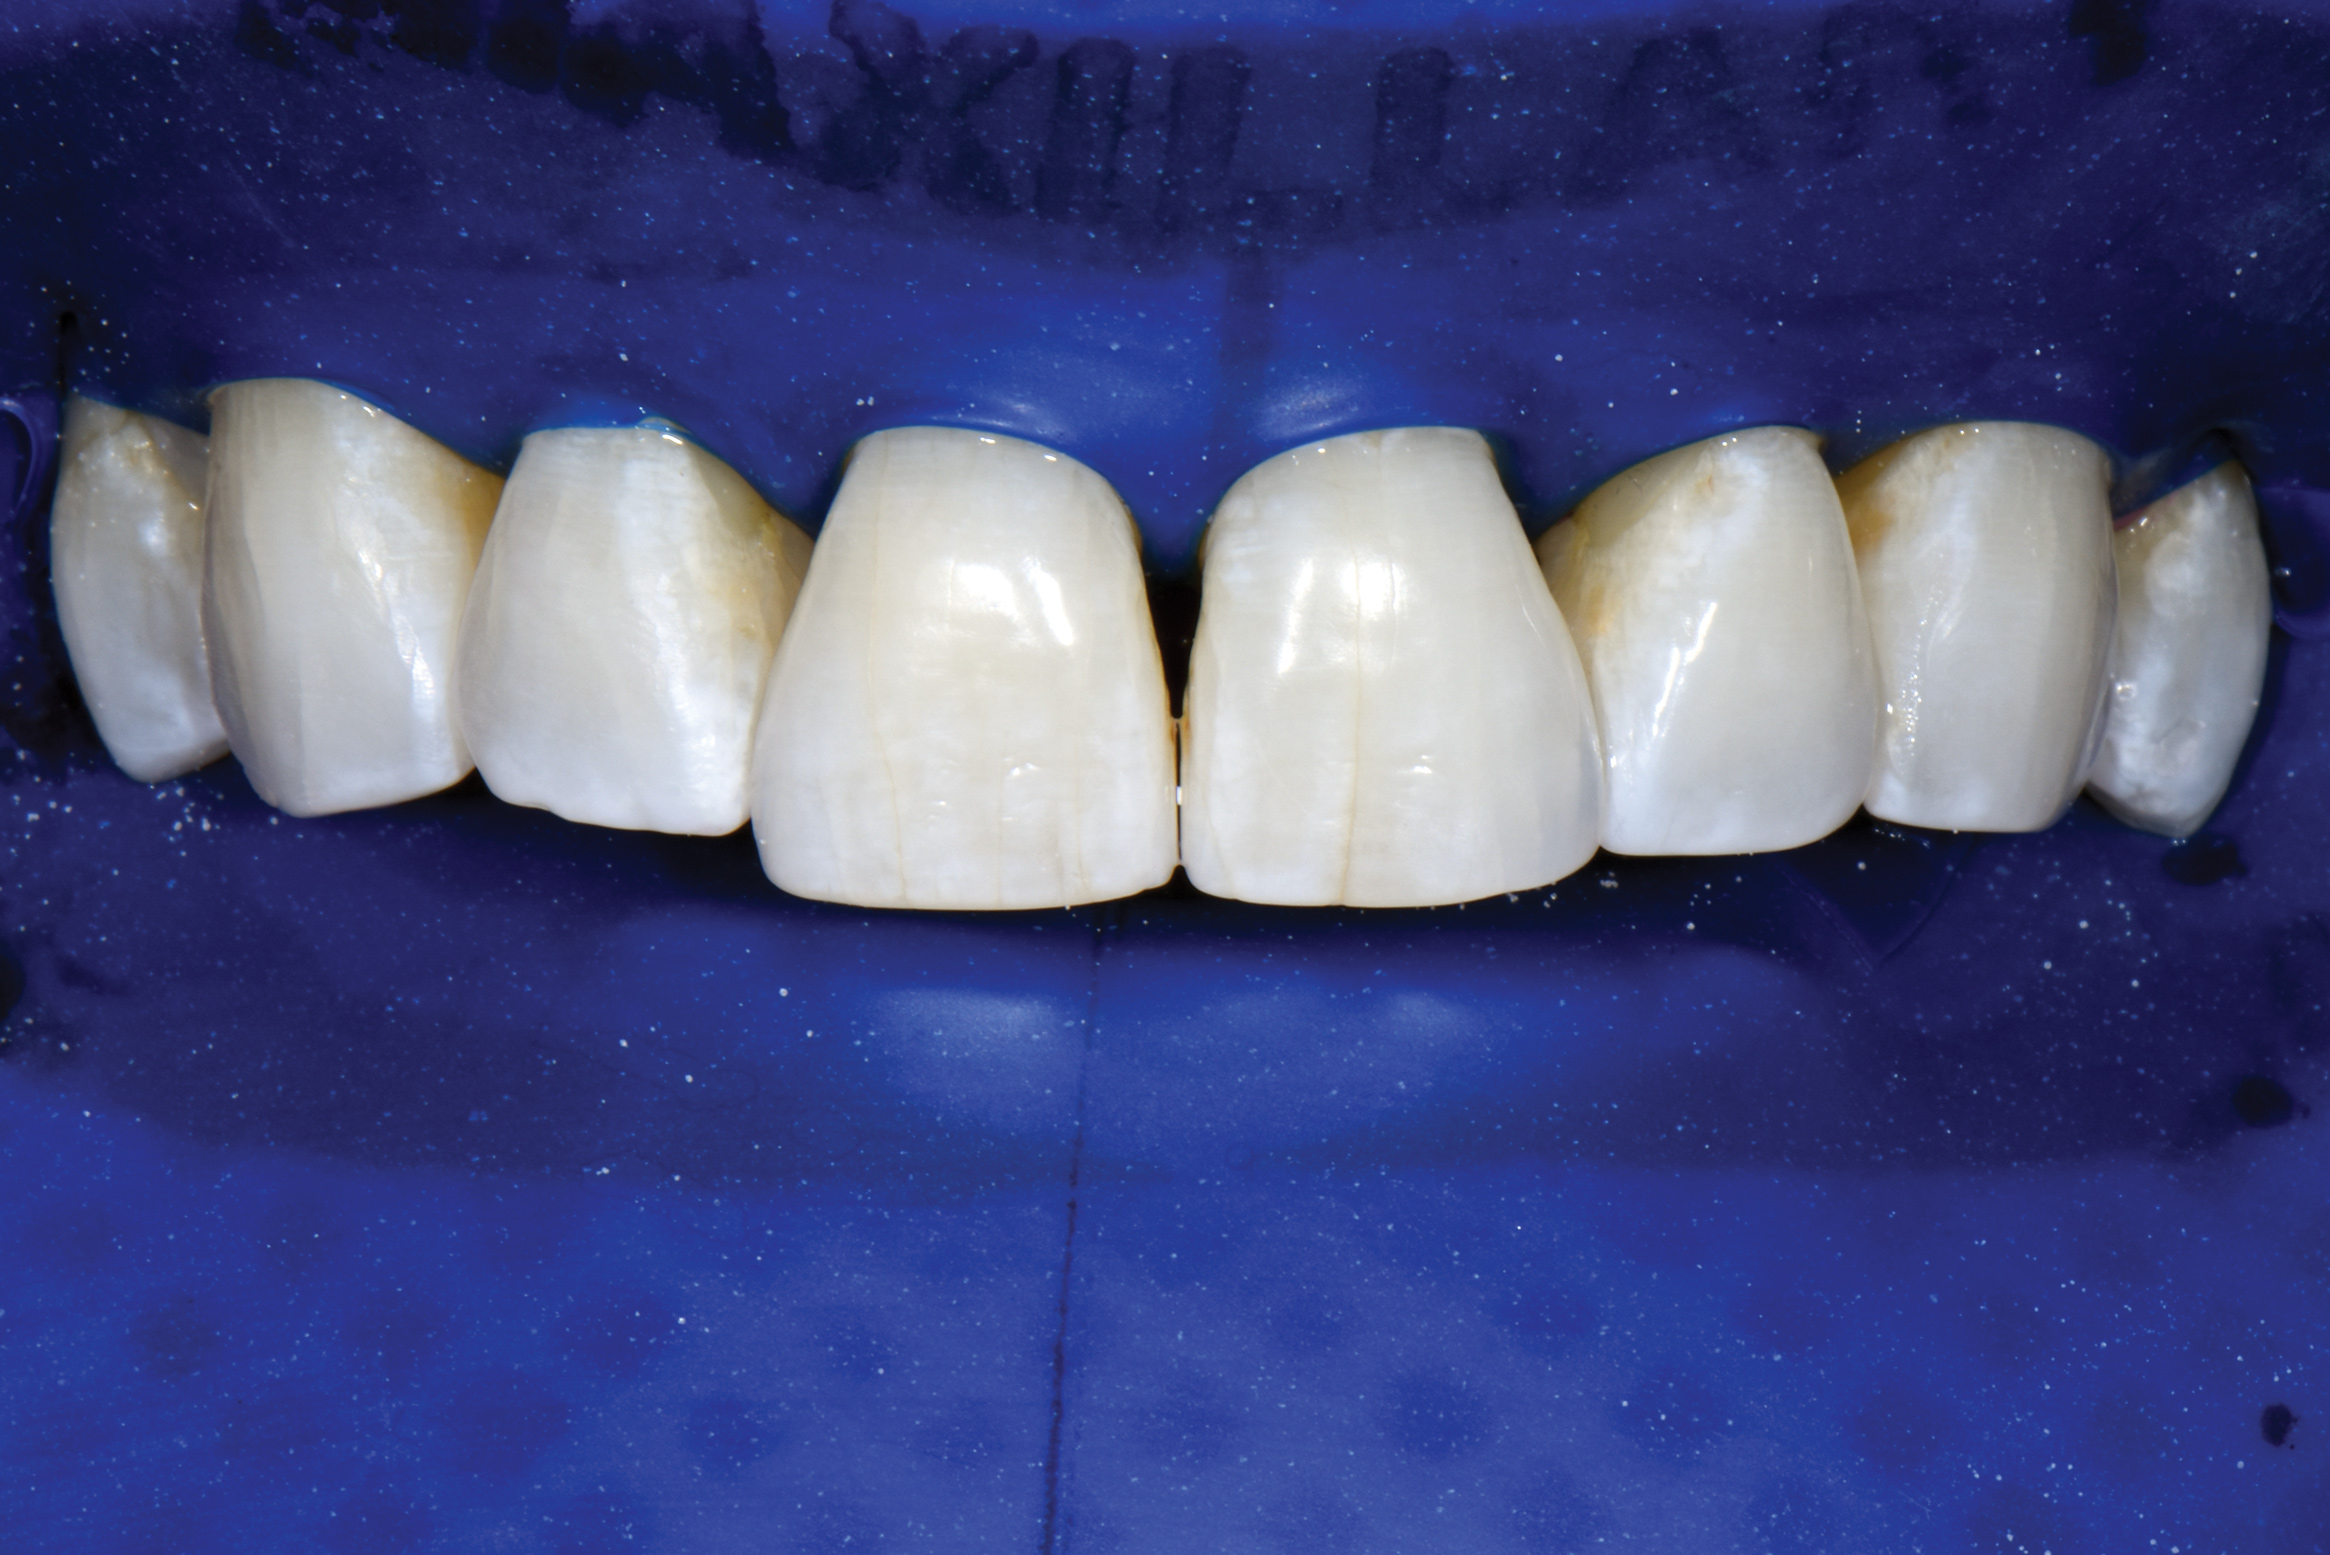

With these limitations acknowledged, visual inspection of tooth preparations after air abrasion reveals that this modality is effective in removing remnant restorative materials, stains, and temporary cement, leaving a clean, matte surface for bonding (Figure 11 through Figure 14). Air abrasion also can smooth the internal aspects of a cavity preparation to help enable better adaptation of the restorative material (Figure 15 and Figure 16). The technique-sensitive nature of adhesive bonding may justify this extra procedure to ensure a clean, smooth preparation.

Fig 13. Crown preparations with temporary cement remnants prior to air abrasion (Fig 13) and after air abrasion (Fig 14) (case by Mohammed Badahman, DDS).

Fig 14. Crown preparations with temporary cement remnants prior to air abrasion (Fig 13) and after air abrasion (Fig 14) (case by Mohammed Badahman, DDS).